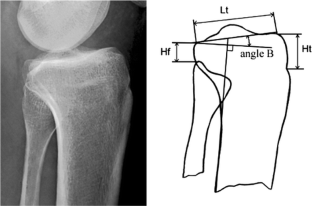

Fig. 1